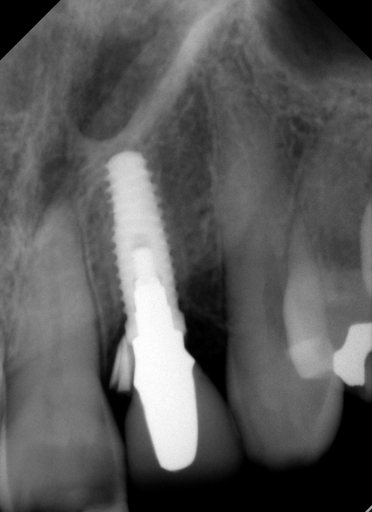

We couldn’t believe what we saw! How on earth did I leave such a large piece of cement? I mean, seriously, I was using RMGI cement that is easy to clean up, and we had done a custom abutment, so the margins were super accessible. We went after the debris and felt like we got some out, but honestly not as much as we expected, so we took another radiograph to see how we were doing. Here’s what we saw:

We were saying, “What’s going on? How did this piece move from one side to the other and not come out?” It was clear we needed to remove the restoration so we could better visualize things; needless to say, this was super disappointing.